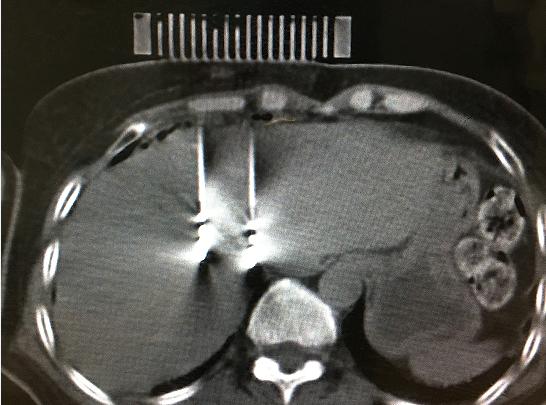

9月11日,醫(yī)院腫瘤科張開賢主任醫(yī)師團隊對一例肝癌術(shù)后復(fù)發(fā)的患者成功進行了國內(nèi)首例3D打印共面模板引導(dǎo)下的微波消融術(shù),標(biāo)志著肝癌進入精準(zhǔn)微波消融時代。

患者女性,57歲,肝癌術(shù)后5月復(fù)發(fā),病灶6.0cmx6.0cm大小,位于肝臟的右葉,靠近隔頂部,經(jīng)過多學(xué)科討論,決定實施經(jīng)皮微波消融術(shù),由于腫瘤體積較大,需要同時使用兩根消融天線進行多平面消融,為確保療效,兩根消融天線需要平行等距,但由于肝臟是不斷運動的臟器,徒手操作有一定技術(shù)難度,往往需要多次穿刺調(diào)整進針方向才能達到上述要求,為此,滕州市中心人民醫(yī)院腫瘤科張開賢主任醫(yī)師團隊借鑒既往采用模板引導(dǎo)放射性粒子植入的經(jīng)驗,創(chuàng)造性地將3D打印模板技術(shù)應(yīng)用于該例患者的消融治療,在模板引導(dǎo)下在兩個平面上平行等距插入兩根消融天線,經(jīng)過18分鐘的消融,腫瘤完全壞死,達到完全消融,患者正在術(shù)后康復(fù)之中。

3D打印模板引導(dǎo)消融的優(yōu)點:迅速將腫瘤與模板“固定”,防止因肝臟運動導(dǎo)致的穿刺不確定性;確保兩根消融天線平行等距,使熱場分布更加均勻;一次性穿刺布針成功,避免反復(fù)穿刺導(dǎo)致的腫瘤種植性轉(zhuǎn)移;模板對消融天線起到固定,防止因來回移動導(dǎo)致的消融天線位置的改變。據(jù)悉,這是國內(nèi)首例3D打印模板引導(dǎo)下的肝癌微波消融術(shù),這一技術(shù)的推廣應(yīng)用必將造福更多的腫瘤患者。(腫瘤一科 胡苗苗)